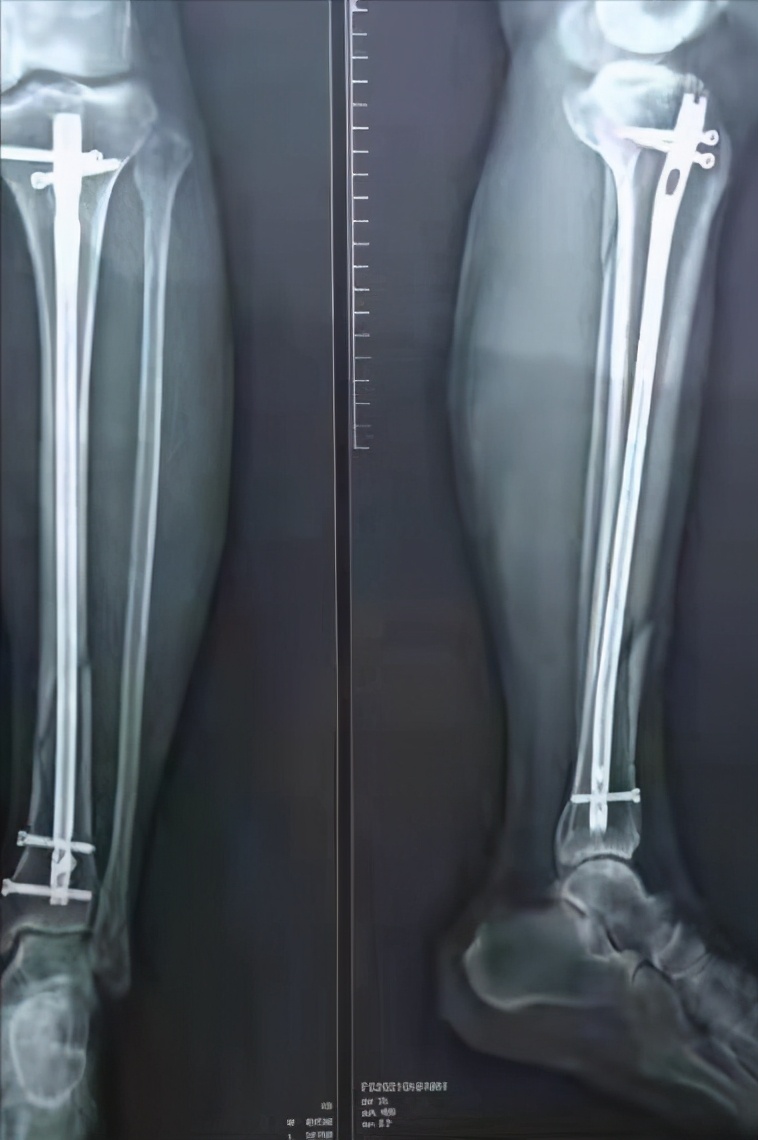

回, 脛骨高原骨折に対し観血的治療を行った症 例について, その治療方法と術後成績について 検討したので報告する 対象および方法 対象は脛骨高原骨折に対して観血的治療を施 行した9例9関 節である 受傷時年齢は37~86 歳 (平均565歳) であった 脛骨近位部骨折の治療法 保存療法 :骨折が軽傷であった場合、ギプス固定をする 手術 内固定法:割れた骨や骨のかけらを元の位置に戻し、プレート固定を行う 小侵襲内固定術:割れた骨や骨のかけらを元の位置に戻し、プレートやスクリューを使って固定する リハビリテーション:足の筋力の改善、膝の動きを改善する 骨がくっつくまでに12か月かかる場合が多い 骨が弱かったり 脛骨腓骨骨折プレート固定術をするとおおよその目安の期間は以下になります。 (骨折箇所によって安静期間や固定期間は違いますが、今回の足の手術の場合ということで参考までに) 荷重訓練は6週間後から開始(最初は1/3荷重から) ↓ 全荷重が3ヶ月後 ↓ プレートを抜くのは1年後 しばらくプレートは入ったままの生活になります。 プレートのビスは抜けないのか心配 昔は「ビス

骨折から1年と1か月、とうとうプレートとボルトを抜く抜釘手術を受けてきました。 骨折の経緯は下記 アイスクライミングで右足果部 腓骨・脛骨骨折 復帰までの記録 ①受傷から手術~退院まで ムカデのおにいさんのブログ アイスクライミングで右足果部腓骨・脛骨骨折 復帰までの記録ずれがない骨折であれば、ギプス装着を数週間行うことで治癒することが多いとされています。 手術 骨のずれが大きいなどの場合には、骨の位置を正しい位置に戻す手術が必要です。 足関節の骨折では、骨片の配置を正しく整え、また治癒中に再び骨片がずれることのないよう、観血的整復固定術(ORIF)と呼ばれる手術を行うことがあります。 患部を切開して、折れた骨を適切な位置に戻し 骨折手術の方法 骨折手術には種類が複数あり、状態によって手術法が異なります。 ・ピンニング 折れた骨同士を挿入したピンで固定する方法で、骨が折れたことでずれた場合などに使用されます。 ・スクリュー固定 ネジで骨折部を止める方法で、ピンニングと同じく比較的単純な骨折の場合に使用されます。 ・プレート固定 骨折した部分をスクリューとプレートで固定させる方法です